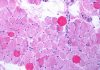

“L’immunoncologia ha aperto una nuova era nel trattamento dei tumori – spiega Filippo de Braud, professore ordinario di Oncologia medica all’Università degli Studi di Milano e direttore Dipartimento e Divisione di Oncologia medica della Fondazione Irccs Istituto nazionale tumori di Milano – E’ in grado di stimolare il sistema immunitario contro il cancro e di migliorare in maniera significativa la sopravvivenza, con una buona qualità di vita. I farmaci immunoncologici tolgono il ‘freno’, costituito dai recettori CTLA-4 e PD-1, con cui il tumore blocca la risposta del sistema immunitario. I risultati ottenuti sono importantissimi e queste terapie, utilizzate da sole o in combinazione, hanno profondamente modificato lo standard di cura in molte neoplasie, dal melanoma al carcinoma del polmone, a quello del rene, fino al mesotelioma pleurico e ai tumori gastrointestinali. L’Italia ha svolto un ruolo fondamentale nello sviluppo di queste molecole innovative”.